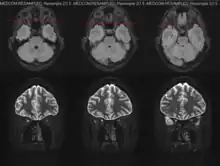

Para el diagnóstico pueden ser necesarios diferentes procedimientos, como una valoración oftalmológica completa, con examen de la agudeza visual y la capacidad de visión de colores. También se realizan una observación del fondo de ojo mediante oftalmoscopia y estudios como la resonancia magnética cerebral.